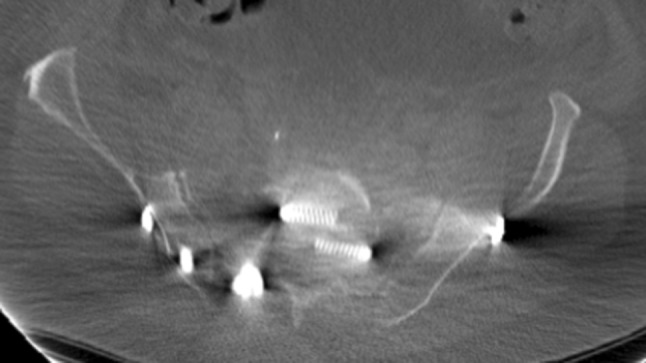

Fig. 2.

Penetration of posterior SI-screw in the S1-canal

The eight patients with mal-placed implants consisted of three patients with SI-screws, of which 1 SI-screw penetrated to the ipsilateral S1 root, 1 SI-screw penetrated the contralateral sacral wall inducing L5-root symptom and the third case was bilateral SI-screws causing anterior displacement of the sacral body causing L5-S1 symptoms (Figs. 1, 2, 3). In addition, there were three cases of screw penetration to the hip joint following anterior column fixation of acetabular fractures, whereof 2 were found early on the post-operative CT scans, and 1 was found during THR surgery 2.5 years later. Finally, there was 1 case with 2 SI-screws who needed screw tightening. The last case of mal-placed implant was an anterior SI-joint plate placed too medial and thereby causing local L5-root symptom. Implant failure occurred in six cases: 3 posterior wall acetabular fractures with loss of reduction, 2 anterior symphyseal plates with loss of reduction and 1 plated trans iliac wing fracture with loss of reduction. Details on patients reoperated due to hardware-related problems are given in Table 5. The median (IQR) hospital length of stay was 23 (10–44) days for patients who underwent a reoperation during their primary hospital stay, compared to 18 (10–25) for surgically treated patients who were not reoperated (p = 0.2).